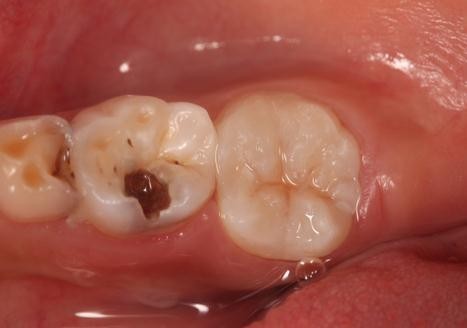

树脂修复病例

患者,女,右下6龋坏要求修复,平素体质一般,无药物、食物过敏史,无高血压、心脏病等系统病史。

去腐,树脂修复

效果很好,患者满意